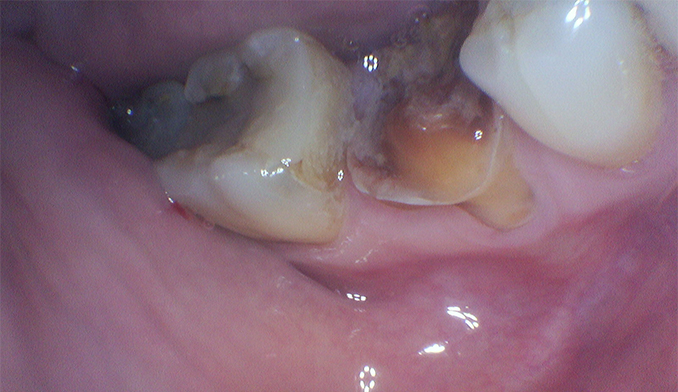

Molar Extraction, Bone Grafting, and Implant Placement

The patient’s lower right molar was severely damaged and could not be saved. After removing the tooth, we performed bone grafting to preserve the bone structure, ensuring a strong foundation for future treatment. Four months later, after proper healing, a dental implant was placed to restore function and maintain jaw health.